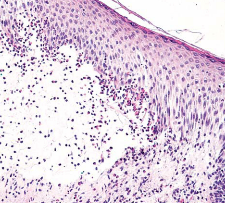

Keratinocytic neoplasms that develop in sun-damaged skin, commonly on the face or backs of hands. The basal keratinocytes of the stratum spongiosum display significant atypia, as well as hyperkeratosis and parakeratosis. This lesion is a precursor to SCC.

(image displays parakeratosis)

A

Actinic Keratosis

(image displays cytologic atypia of basal keratinocytes)